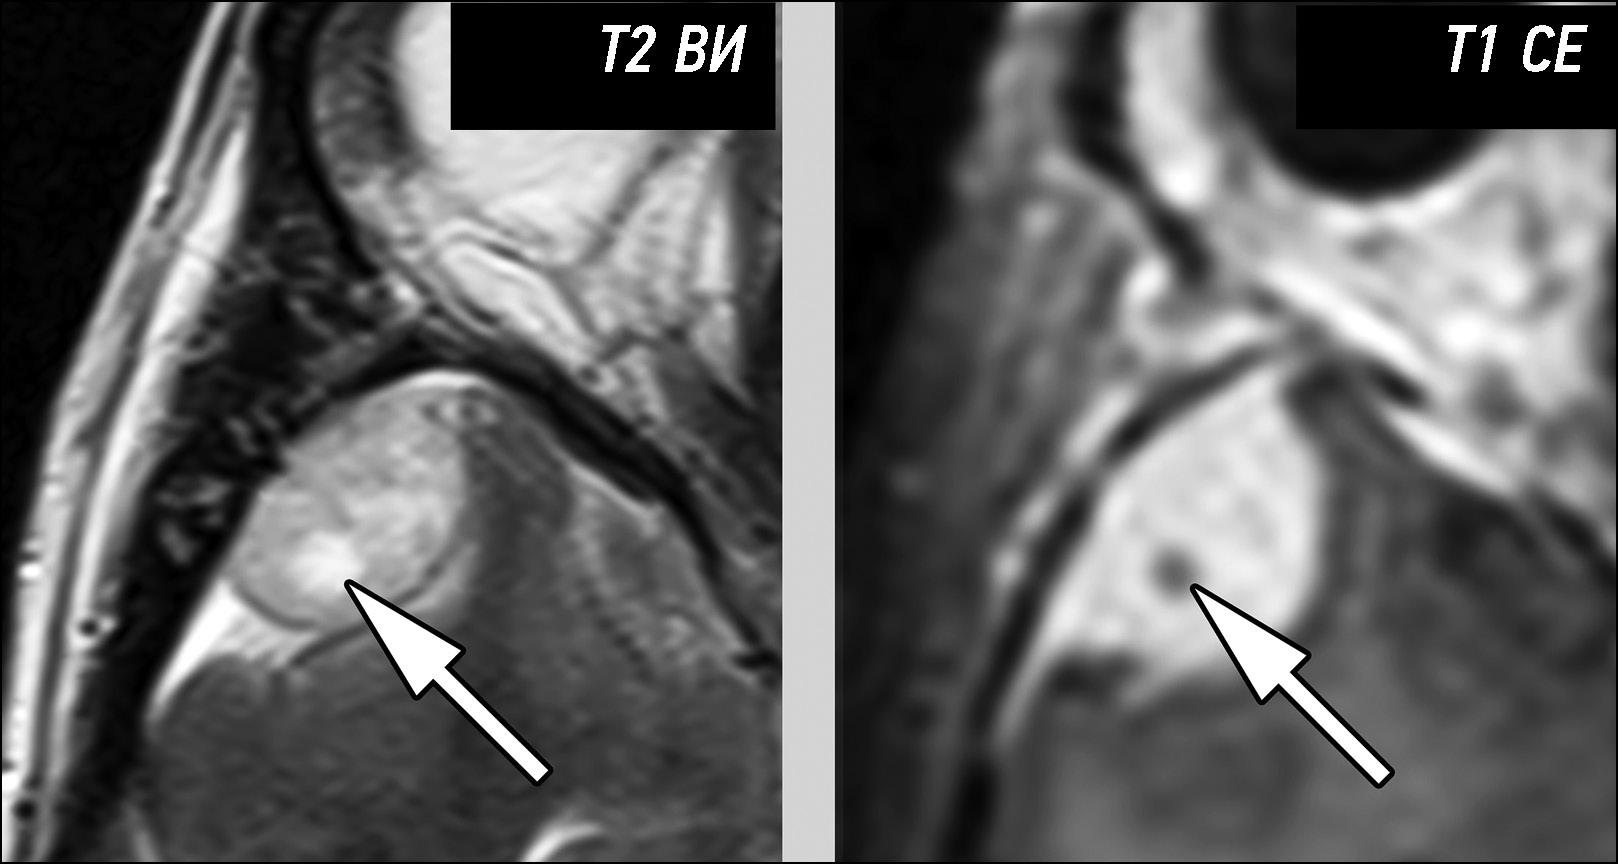

Rare complications of acute epididymitis include ischemia and infarction of the testicles. Both clinically and radiologically, it is challenging to distinguish testicular torsion. In this article we have tried to expand the library of digital images of radiological diagnostic methods used for fast and accurate differential diagnostics. This case emphasizes the significance of a comprehensive radiological assessment and how a multidisciplinary approach is necessary to guarantee an accurate diagnosis. A 24-year-old man experienced severe left testicular pain and came to the hospital 2 weeks later. At the radiology department, he reported that he had for some time painful ejaculations, pain during intercourse (dyspareunia), scrotal redness/swelling, genital inflammation, chills, swollen inguinal lymph nodes, dysuria, and scrotal pain. All diagnostic procedures were performed, first ultrasonography and then magnetic resonance imaging, as required by the urologist. The imaging studies revealed left testicular ischemia, and based on the referred clinical history, a chronic orchid-epididymitis was suspected. Thus, the condition was resolved, not with a left orchidectomy but with medical therapy because the ischemia area was not too large. The patient also had a left varicocele. Images acquired with different magnetic resonance imaging sequences were carefully examined. A rare instance of epididymal orchitis is described as a potentially dangerous complication of epididymitis and must be considered if sudden, severe scrotal pain is experienced to avoid severe consequences. This case can help with optimal patient management and prevent unnecessary interventions.